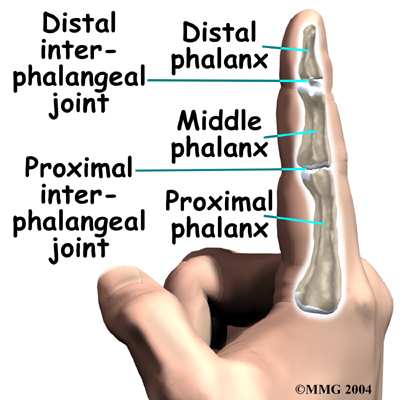

The bones in the palm of the hand are called metacarpals. One metacarpal connects to each finger and thumb. Small bone shafts called phalanges line up to form each finger and thumb.

The bones in the palm of the hand are called metacarpals. One metacarpal connects to each finger and thumb. Small bone shafts called phalanges line up to form each finger and thumb.

The main knuckle joint is formed by the connection of the phalanges to the metacarpals. This joint is called the metacarpophalangeal joint (MCP joint). The MCP joint acts like a hinge when you bend and straighten your fingers and thumb.

The in each finger are separated by two joints, called interphalangeal joints (IP joints). The one closest to the MCP joint (knuckle) is called the proximal IP joint (PIP joint). The joint near the end of the finger is called the distal IP joint (DIP joint). The thumb only has one IP joint between the two thumb bones. The IP joints of the digits also work like hinge joints when you bend and straighten your hand.